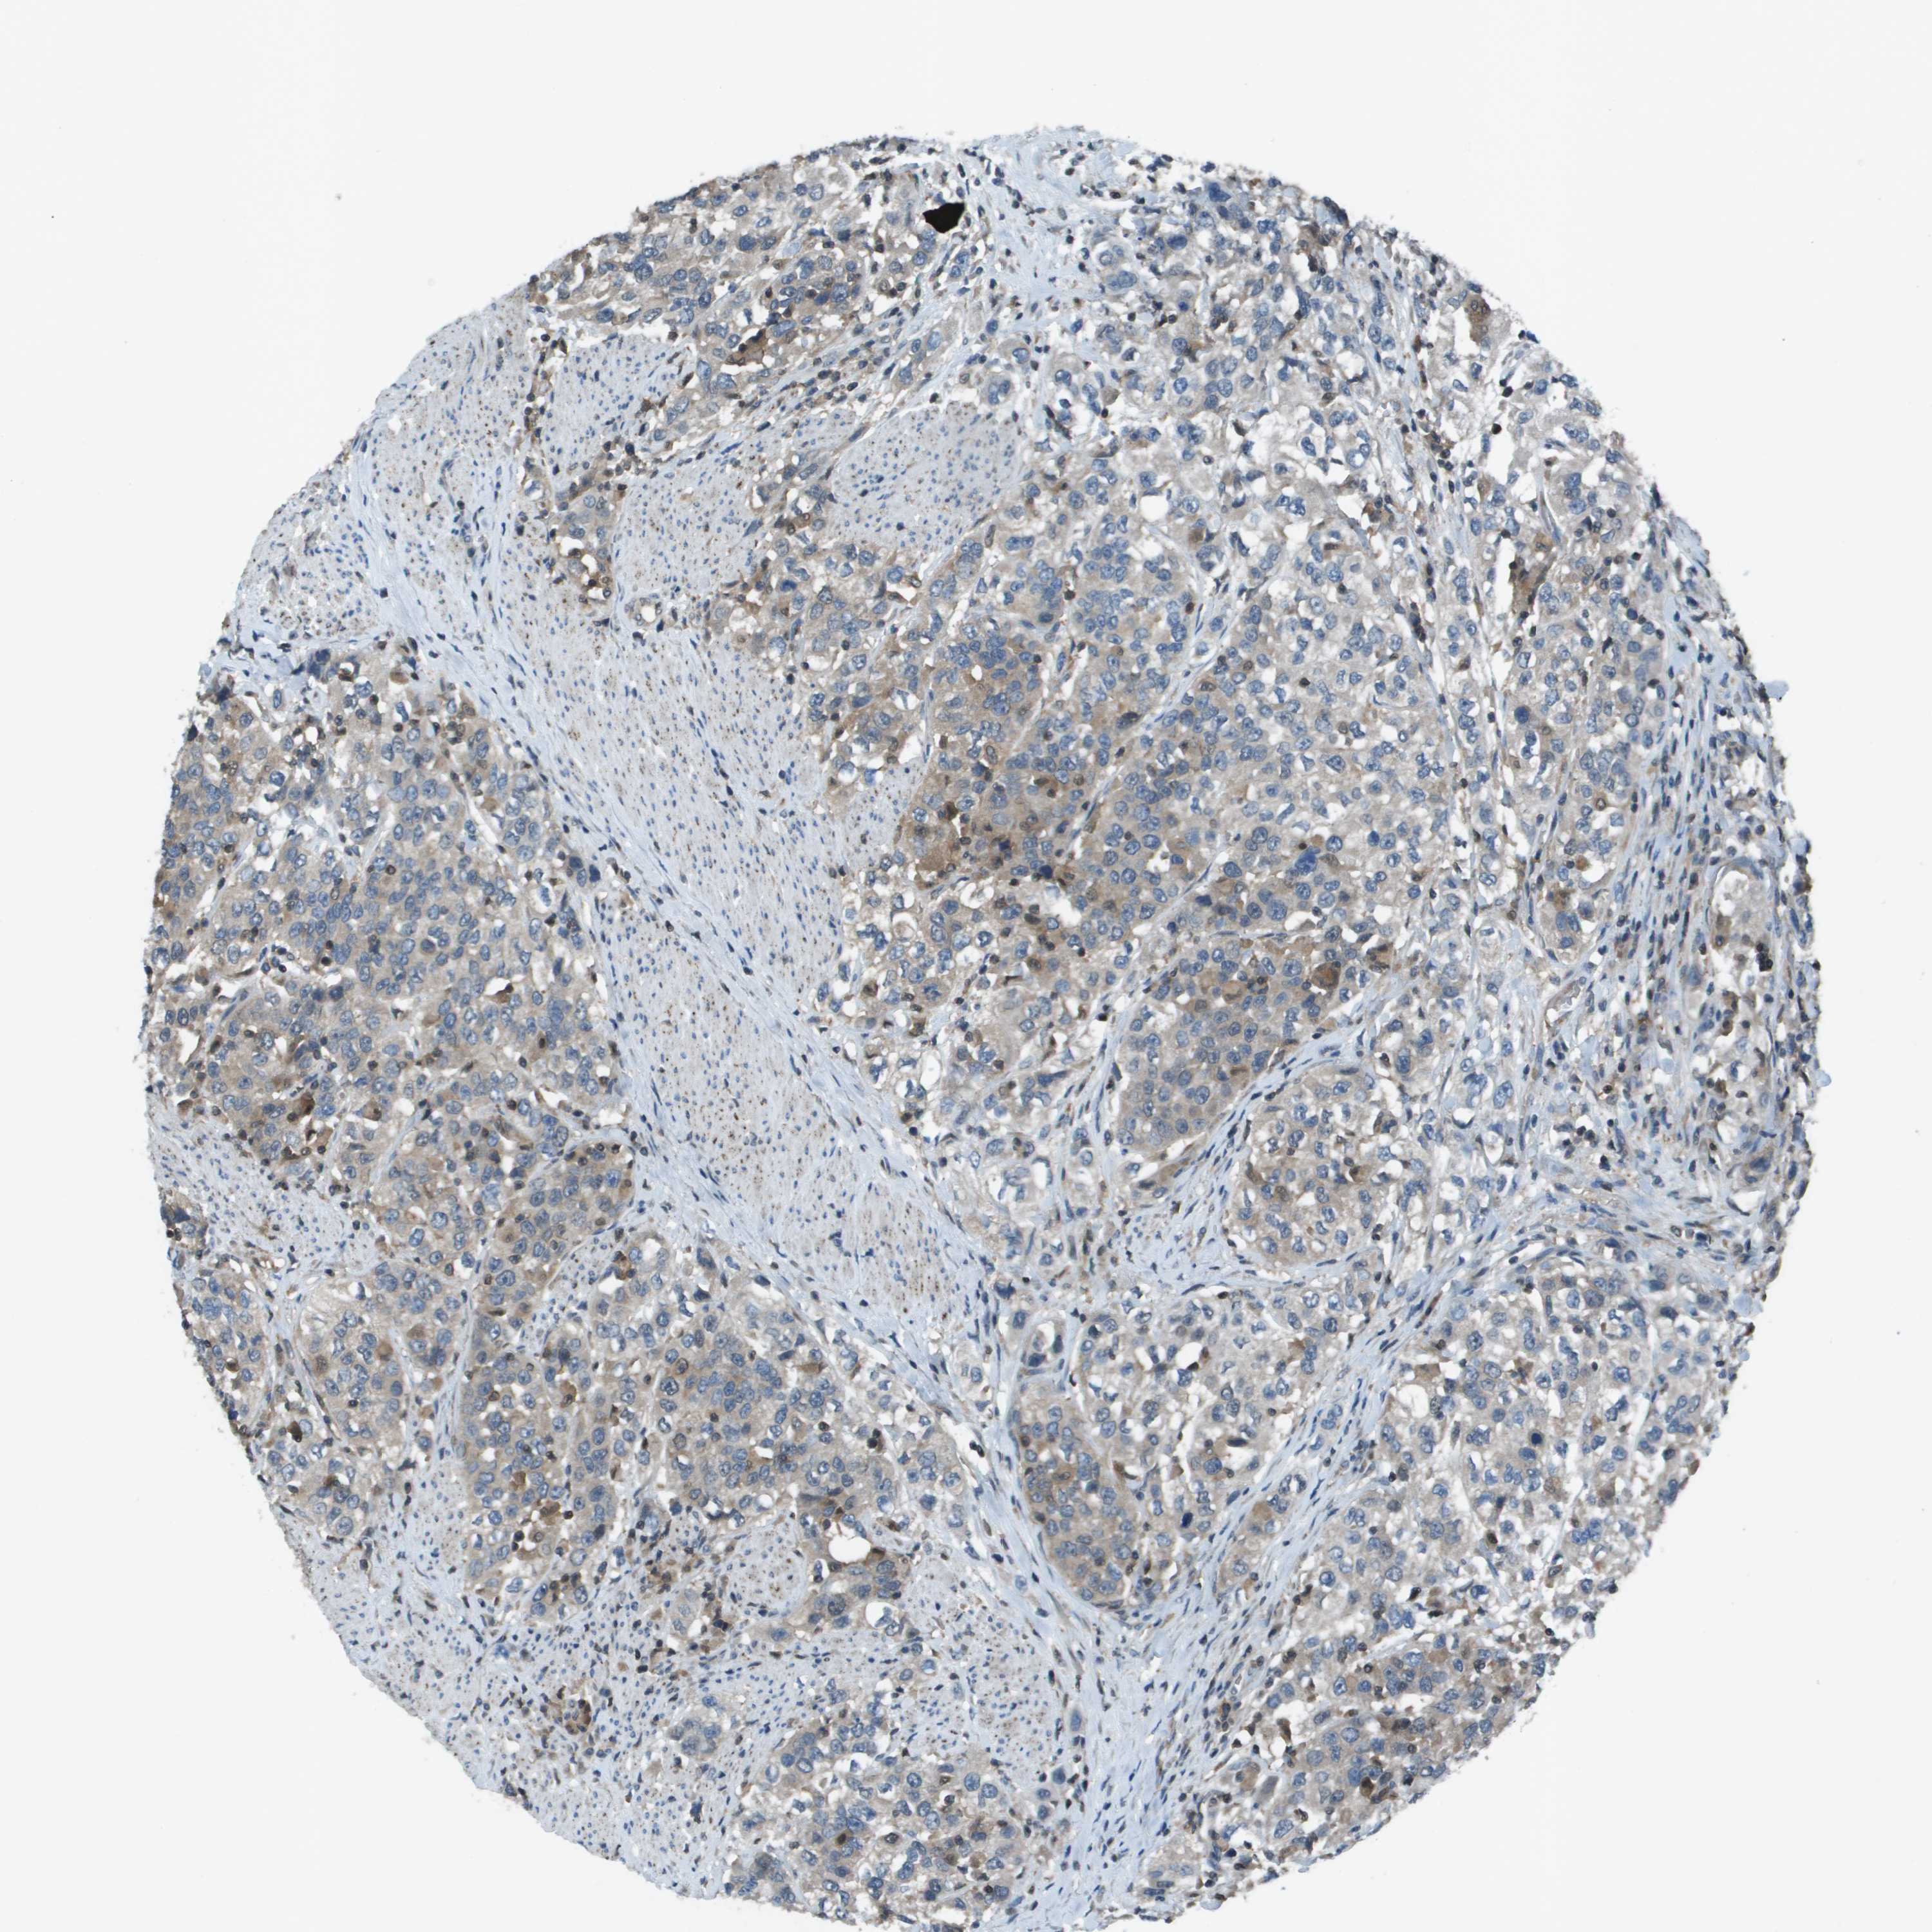

UROTHELIAL CANCER - Protein expressioni

A mouse-over function shows sample information and annotation data. Click on an image to view it in a full screen mode. Samples can be filtered based on level of antibody staining by selecting one or several of the following categories: high, medium, low and not detected. The assay and annotation is described here.

Note that samples used for immunohistochemistry by the Human Protein Atlas do not correspond to samples in the TCGA dataset.

Antibody stainingi

Antibody staining in the annotated cell types in the current human tissue is reported as not detected, low, medium, or high, based on conventional immunohistochemistry profiling in selected tissues. This score is based on the combination of the staining intensity and fraction of stained cells.

Each image is clickable and will lead to virtual microscopy that enables deeper exploration of all samples and also displays staining intensity scores, fraction scores and subcellular localization as well as patient and tissue information for each sample.

Antibody HPA011753

Antibody HPA017206

Antibody CAB004347

Staining

High

Medium

Low

Not detected

Intensity

Strong

Moderate

Weak

Negative

Quantity

>75%

75%-25%

<25%

None

Location

Nuclear

Cytoplasmic/membranous

Cytoplasmic/membranous,nuclear

Urothelial carcinoma, Low grade

Urothelial carcinoma, High grade